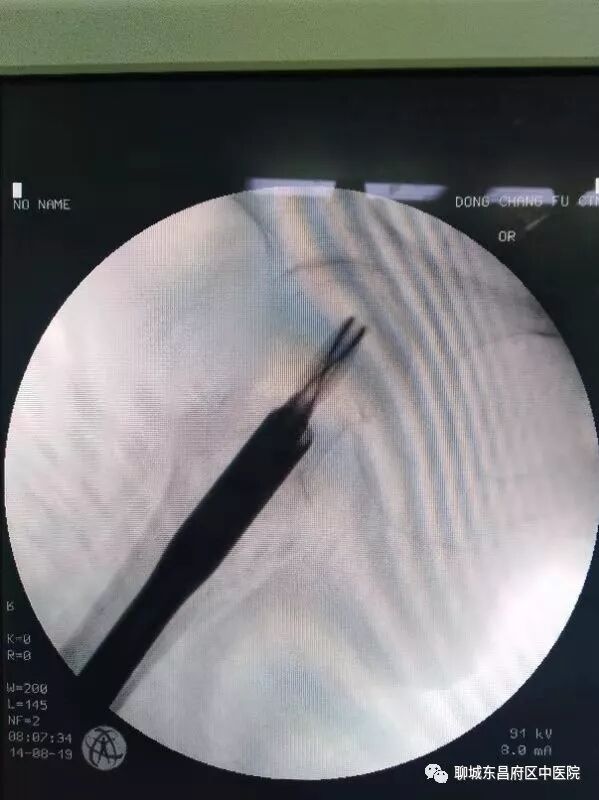

昨日,我院120接入一91岁高龄右股骨粗隆间骨折患者,入院后骨一科主任郭文青高度重视,对患者进行了初步查体,组织科室进行了风险评估,完善了入院相关检查,请麻醉科韩青主任进行了术前会诊。 经过详细的术前准备后,今日上午给予闭合复位PFNA内固定。患者90余岁高龄,各脏器已经严重衰老,对麻醉及手术的耐受能力已经很差,这已经给麻醉师提出了很严峻的考验,再加上患者驼背畸形,这就给麻醉穿刺带来了更大的困难。但我院手术室的同事们并没有被困难吓到,而是迎难而上,以精湛的技术,凭着过硬的基本功,顺利的完成了穿刺、置管、给药,整个过程患者病情非常稳定。该例股骨粗隆间骨折的手术,对于主刀医生也同样存在很大的困难。其一,该骨折为粉碎性骨折,虽为粗隆间骨折,但接近股骨颈,在复位时股骨头容易旋转,导致闭合复位失败。其二,患者骨质疏松严重,骨皮质很薄,在操作过程中很容易出现新的骨折,这就要求主刀医生在操作过程中要更加细心,准确。郭文青主任利用中医整复技巧,首先顺利的完成了整复,而后郭主任每一步操作都必须准确到位,经过40分钟紧张有序的忙碌,顺利的完成了手术,整个手术过程患者病情稳定,无疼痛及不适,术后往ICU继续治疗。